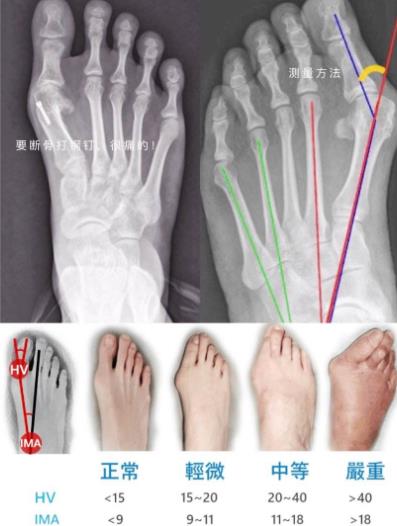

大腳骨手術(shù)前,應(yīng)拍x光片,檢查指關(guān)節(jié)是否有脫位、風(fēng)濕及骨贅大小。外科調(diào)節(jié)可以用腔靜脈后神經(jīng)系統(tǒng)麻醉劑。

大腳骨手術(shù)時(shí),在指骨關(guān)節(jié)后側(cè)制作一個(gè)長(zhǎng)約1cm的弧形微創(chuàng)開(kāi)口,切除皮膚外露的肥大型滑囊。用小止血鉗分離滑膜囊腔內(nèi)暴露的較高骨贅,用高速手電鉆配合特制麻花鉆研磨較高骨贅。然后用小彎剪按大拇趾背側(cè)到達(dá)大拇趾內(nèi)側(cè)遠(yuǎn)端,大拇趾內(nèi)收肌關(guān)節(jié)脆性斷裂,然后縫合滑囊,術(shù)后在第一、二趾間插入成型泡沫塑料墊,用紗布將固定好的大拇趾固定在正確位置,約3周。術(shù)后12天拆線,跖趾關(guān)節(jié)訓(xùn)練3周以上。

2.矯正不盡如人意:是地面骨贅過(guò)少或未斷拇內(nèi)收肌所致,或因適用范圍錯(cuò)誤所致。嚴(yán)重的拇外翻畸形不適合用這種方法矯正,應(yīng)采用大傷口截骨,用縫線與近端骨膜重疊的方法收緊滑囊關(guān)節(jié)囊進(jìn)行矯正。